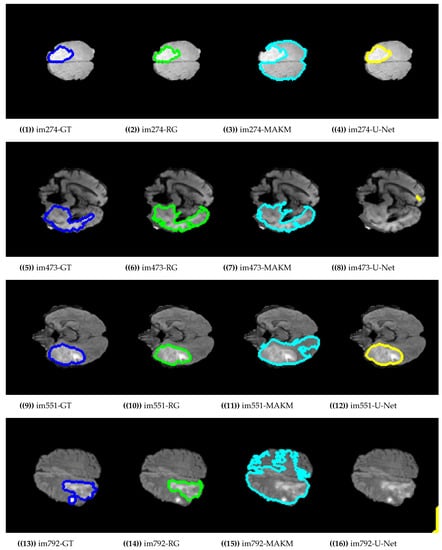

Figure 4 presented the segmentation results of the proposed algorithm, MAKM, and U-Net in terms of ROIs and their respective ground truths. For im274, im473, im551, im1507, im781, and im733 the proposed approach achieved ROIs which were almost the same as their respective ground truths (GTs). The proposed approach resulted in under-segmentation for im792 and im1238 as indicated in Figure 4. For the case of U-Net, the good segmentation results were observed only for im274, im551, im1507, and im781 and unable to detect the tumor region for im473, im792, im733, and im1238. In the case of MAKAM, over-segmentation results were achieved in almost all randomly selected brain images except for im274 where it detected the normal brain image part as abnormal.

Figure 4.

Segmentation results on BRATS2015 dataset.